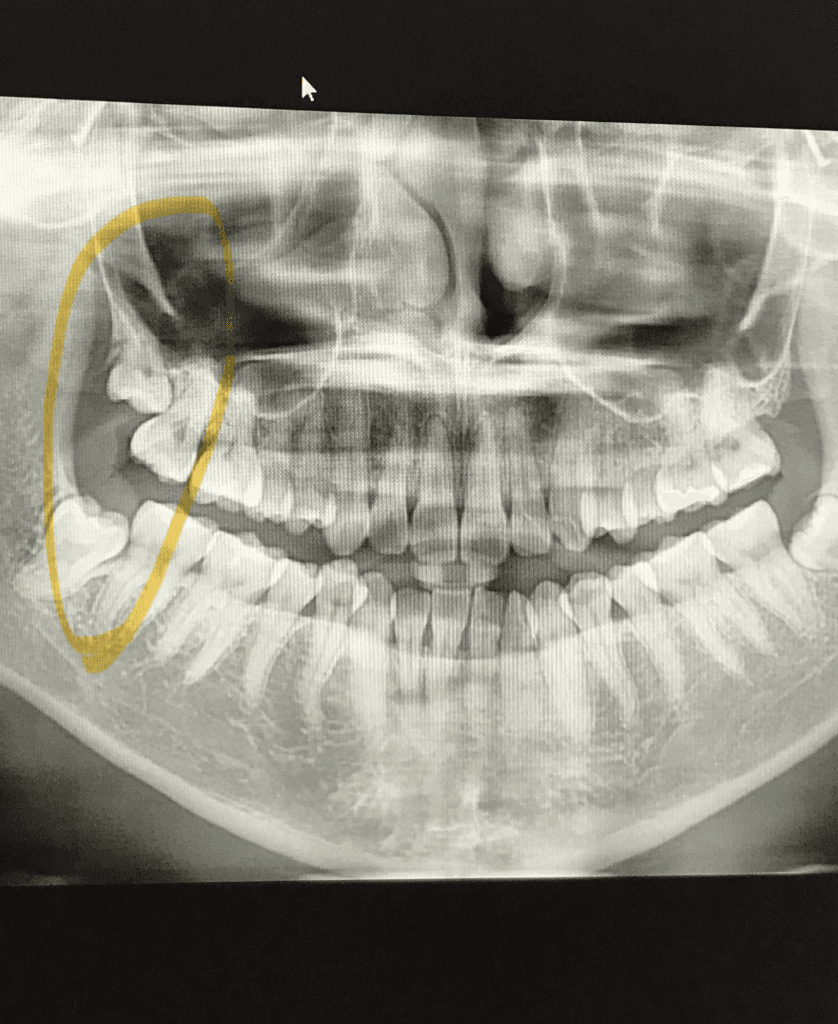

침 치료 부작용이라고만 생각했는데, 혹시 이 증세가 매복되어있는 사랑니때문일 수도 있을까요? 사랑니는 하나도 발치한적 없는데, 문득 우측 상악 사랑니를 혀로 건드리면 조금 아픈 것 같은 느낌이 느껴집니다. 몇년전 촬영한 엑스레이 사진을 첨부합니다.

우선, 사랑니는 때때로 입 안에서 제대로 자리잡지 못하고, 주변 조직에 압력을 가하거나 염증을 유발할 수 있습니다. 이로 인해 저작근 부위의 부기나 통증이 발생할 수 있습니다. 특히 사랑니가 매복되어 있거나 부분적으로만 나온 경우, 입을 크게 벌리거나 오래 씹을 때 불편함을 느낄 수 있습니다. 여러분이 언급하신 것처럼 우측 상악 사랑니를 건드렸을 때 통증이 느껴진다면, 이는 사랑니가 증상의 원인일 가능성을 시사합니다.